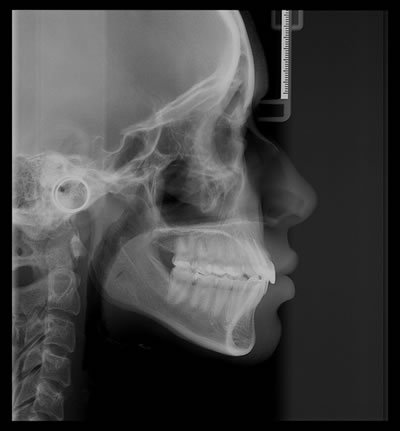

Telerradiografia